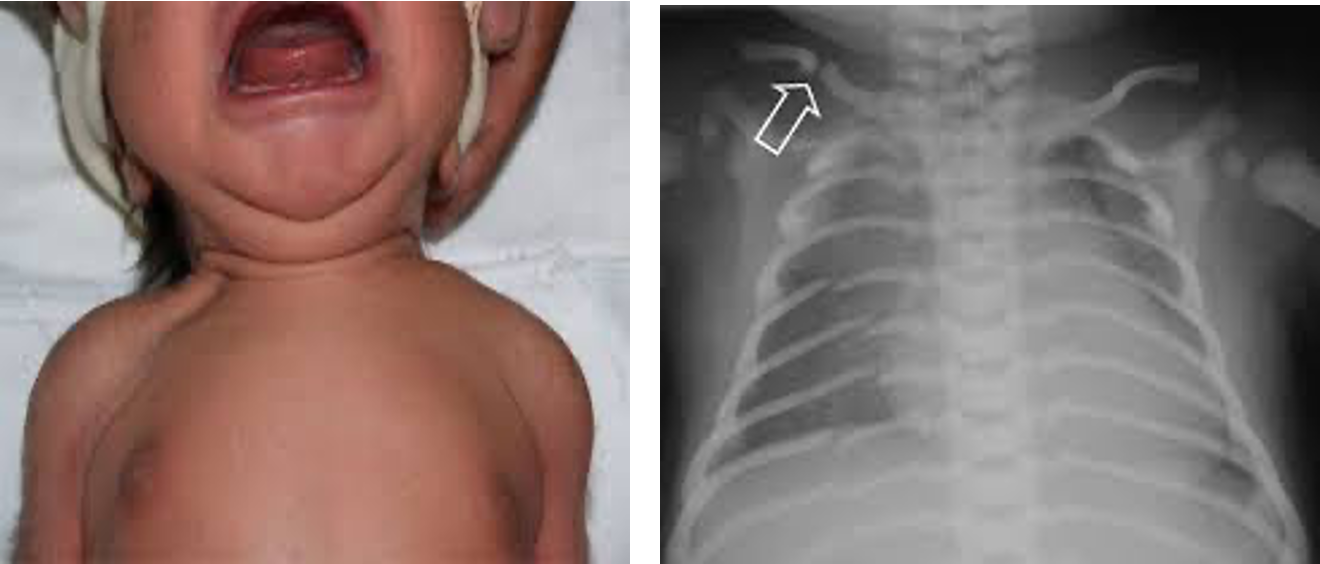

1. Clavicle:

• The most common fracture.

• A snap may be heard at delivery or the infant may have reduced arm movement on the affected side, or a lump from callus formation later, and unilateral absence of Moro reflex.

• Usually from shoulder dystocia.

• Management: nothing as it heals spontaneously.